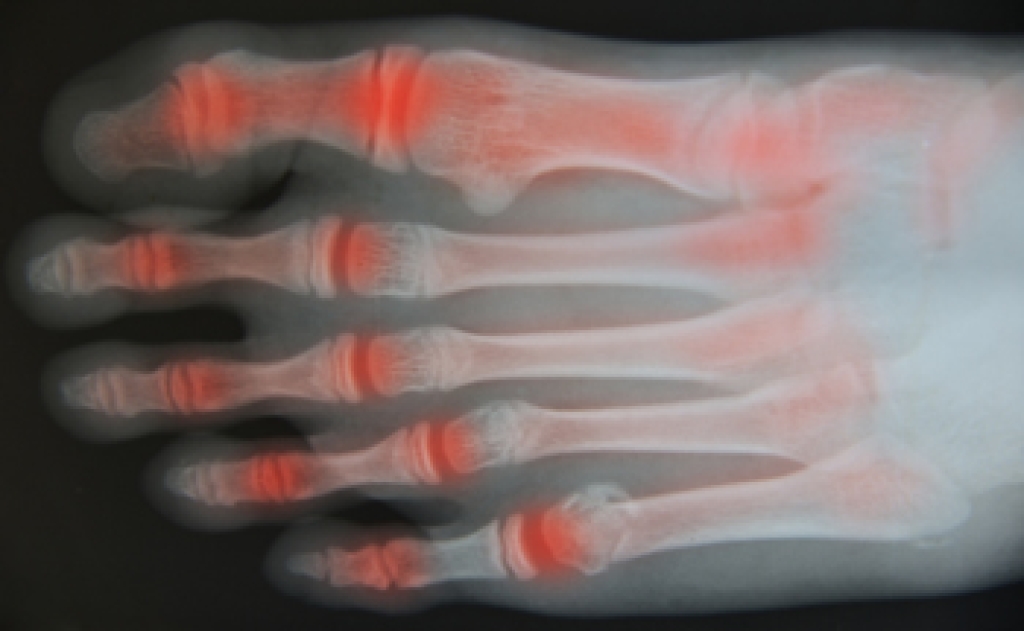

Arthritic Foot Care

Arthritis is a term that is commonly used to describe joint pain. The condition itself can occur to anyone of any age, race, or gender, and there are over 100 types of it. Nevertheless, arthritis is more commonly found in women compared to men, and it is also more prevalent in those who are overweight. The causes of arthritis vary depending on which type of arthritis you have. Osteoarthritis for example, is often caused by injury, while rheumatoid arthritis is caused by a misdirected immune system.

Arthritic symptoms range in severity, and they may come and go. Some symptoms stay the same for several years but could potentially get worse with time. Severe cases of arthritis can prevent its sufferers from performing daily activities and make walking difficult.